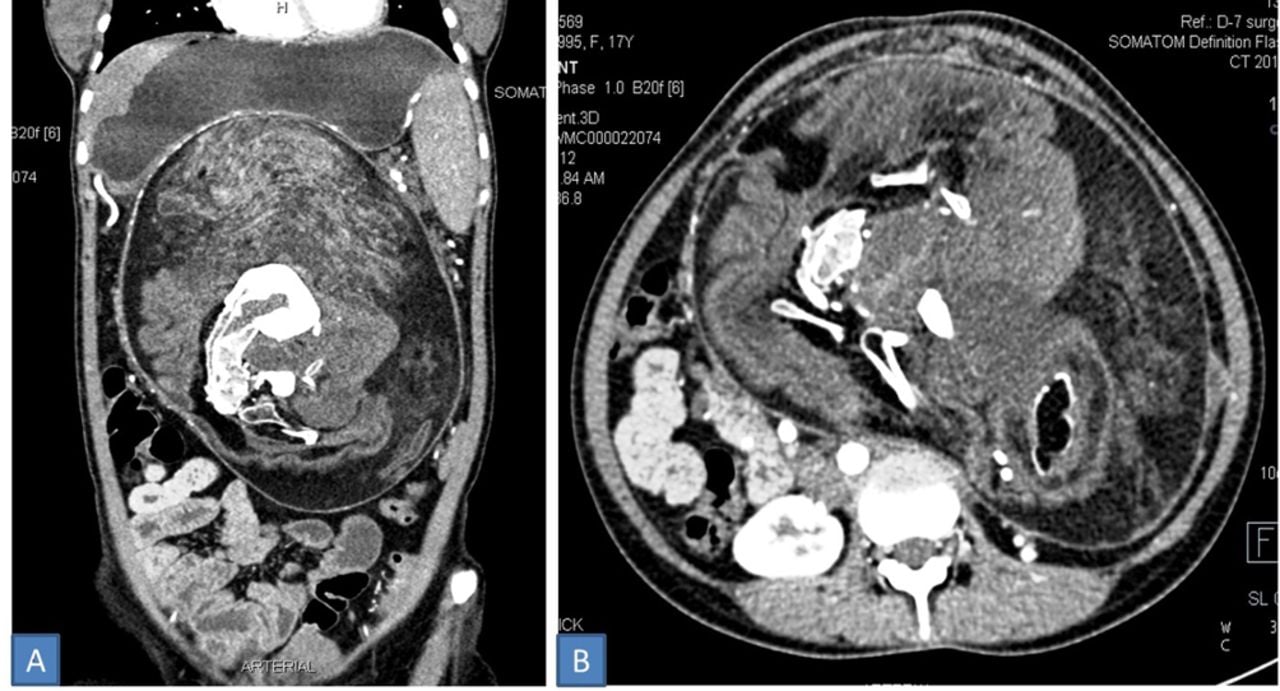

Dans cette situation, le foetus peut alors développer un tronc, des organes et même une colonne vertébrale. C'est grâce à un scanner que les médecins ont donc repéré une masse importante avec une structure complexe mêlant des graisses, des tissus mous et des calcifications. Il ont également détecté l'ébauche d'une colonne vertébrale et de côtes.

Au total, la masse mesurait 30 x 16 x 10 centimètres et pesait une quinzaine de kilos. Sur son enveloppe extérieure, elle était également dotée de poils, de dents et d'os, ainsi que des “bourgeons de membres” qui grandissaient en elle. Précisons que les médecins ont tout de même pensé à faire leur travail en retirant le "jumeau parasite".